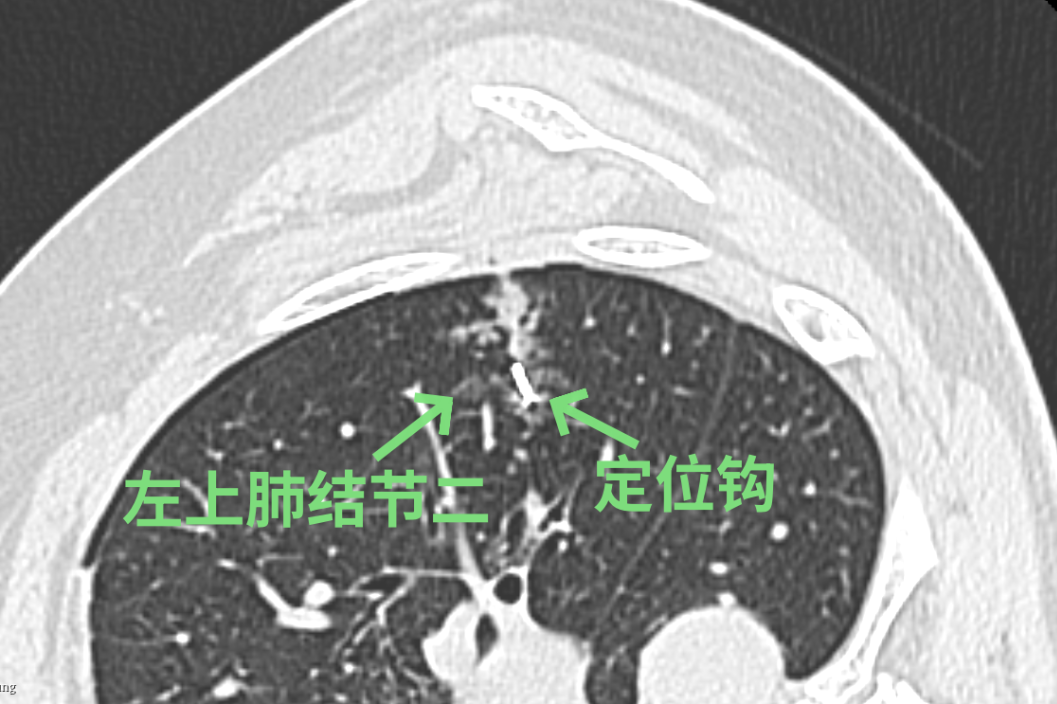

经过徐驯宇主任医师、黄郴副主任医师和王捷阳医师的反复讨论,决定为刘女士实施杂交手术:首先由黄郴和王捷阳在CT引导下为刘女士左上肺的小结节打上金属钩作为标记,然后再对左下肺较深的结节进行热消融治疗;接着由徐驯宇主刀为刘女士进行胸腔镜下左上肺结节的切除。在术中,徐驯宇按照之前在CT引导下置入的金属钩,很快就定位到左上肺的磨玻璃结节,并进行精准的局部切除,整个过程仅耗时30分钟。术后的病理报告显示,这3个结节分别为两个原位癌和一个非典型腺瘤样增生。经过量身定制的杂交手术,刘女士顺利解除了肺部的3个健康隐患,3天就顺利恢复出院。

▲术中结节变化